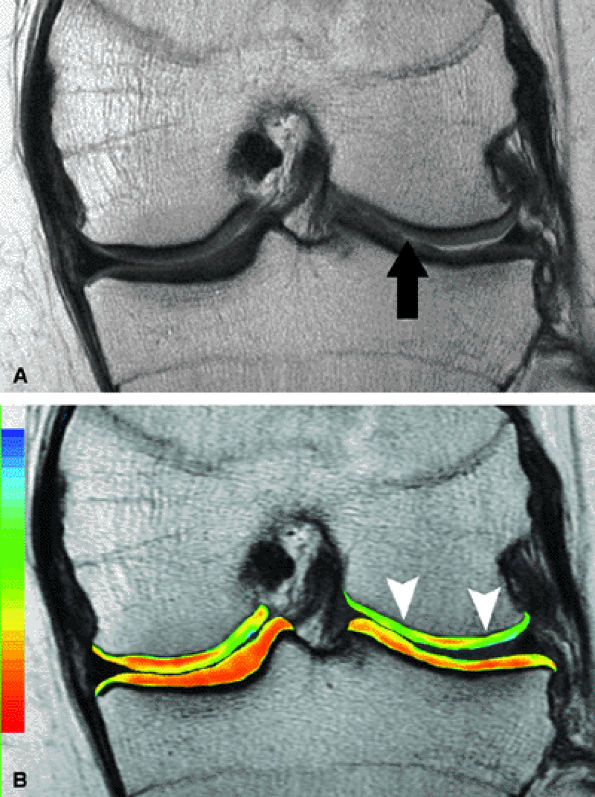

![]() |

FIGURE 7.15 ● (A) Coronal fast spin-echo MR image of the knee in a 15-year-old girl with a previous partial meniscectomy demonstrates mild fibrillation of the cartilage overlying the lateral tibial plateau (arrow). (B) Corresponding quantitative T2 relaxation time map of the femorotibial articular cartilage coded to capture T2 values ranging from 0 to 100 msec demonstrates prolongation of T2 values over the plateau, but with unexpected prolongation over the lateral femoral condyle (arrowheads), which appeared normal on standard fast spin-echo cartilage-sensitive imaging. Green and blue reflect longer T2 values, yellow intermediate, and orange the shorter values.